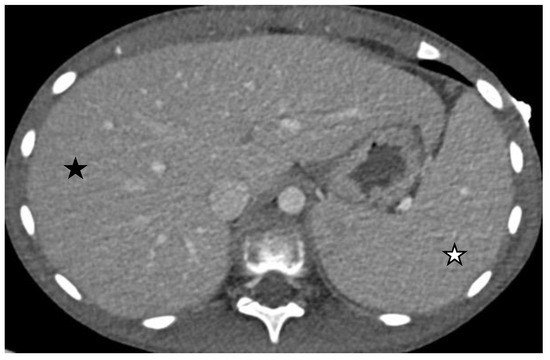

- Size abnormalities of the liver and spleen (Figure 3), kidneys, and pancreas.

- Parenchymal abnormalities of the solid organs (heterogeneous echotexture of the liver or spleen, increased echogenicity of the renal parenchyma compared to the liver, and abnormal or heterogeneous attenuation).

| Hepatic enlargement | 8 | 40% | 15.7% | |

| Splenic enlargement | 9 | 45% | 17.6% | |

| Hepatic enlargement | 5 | 9.8% | 9.8% | |

| Splenic enlargements | 5 | 9.8% | 9.8% | |